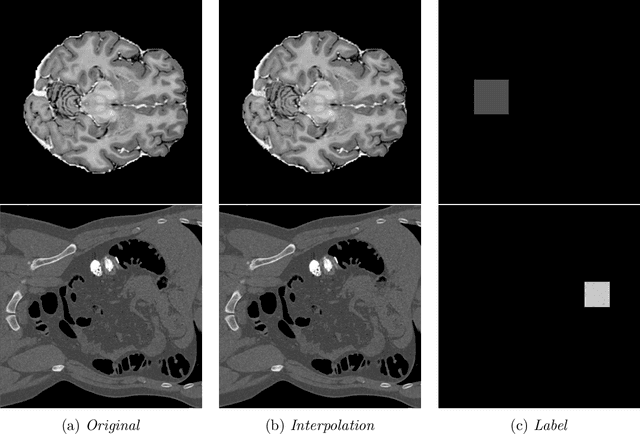

Abstract:In medical imaging, outliers can contain hypo/hyper-intensities, minor deformations, or completely altered anatomy. To detect these irregularities it is helpful to learn the features present in both normal and abnormal images. However this is difficult because of the wide range of possible abnormalities and also the number of ways that normal anatomy can vary naturally. As such, we leverage the natural variations in normal anatomy to create a range of synthetic abnormalities. Specifically, the same patch region is extracted from two independent samples and replaced with an interpolation between both patches. The interpolation factor, patch size, and patch location are randomly sampled from uniform distributions. A wide residual encoder decoder is trained to give a pixel-wise prediction of the patch and its interpolation factor. This encourages the network to learn what features to expect normally and to identify where foreign patterns have been introduced. The estimate of the interpolation factor lends itself nicely to the derivation of an outlier score. Meanwhile the pixel-wise output allows for pixel- and subject- level predictions using the same model.